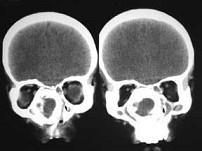

问题 女、14岁,渐进性鼻塞2年余,右眼肿痛数月,CT如图所示,应诊断为()

选项 A.筛骨骨肉瘤 B.筛骨骨纤维异常增殖症 C.筛骨软骨瘤 D.筛骨结核 E.筛骨骨化性纤维瘤

答案 E